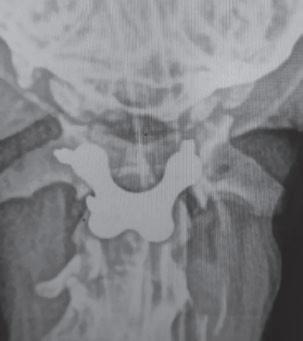

Displasia de cadera (I): etiopatogenia, signos clínicos y pruebas diagnósticas 26

• Displasia de cadera